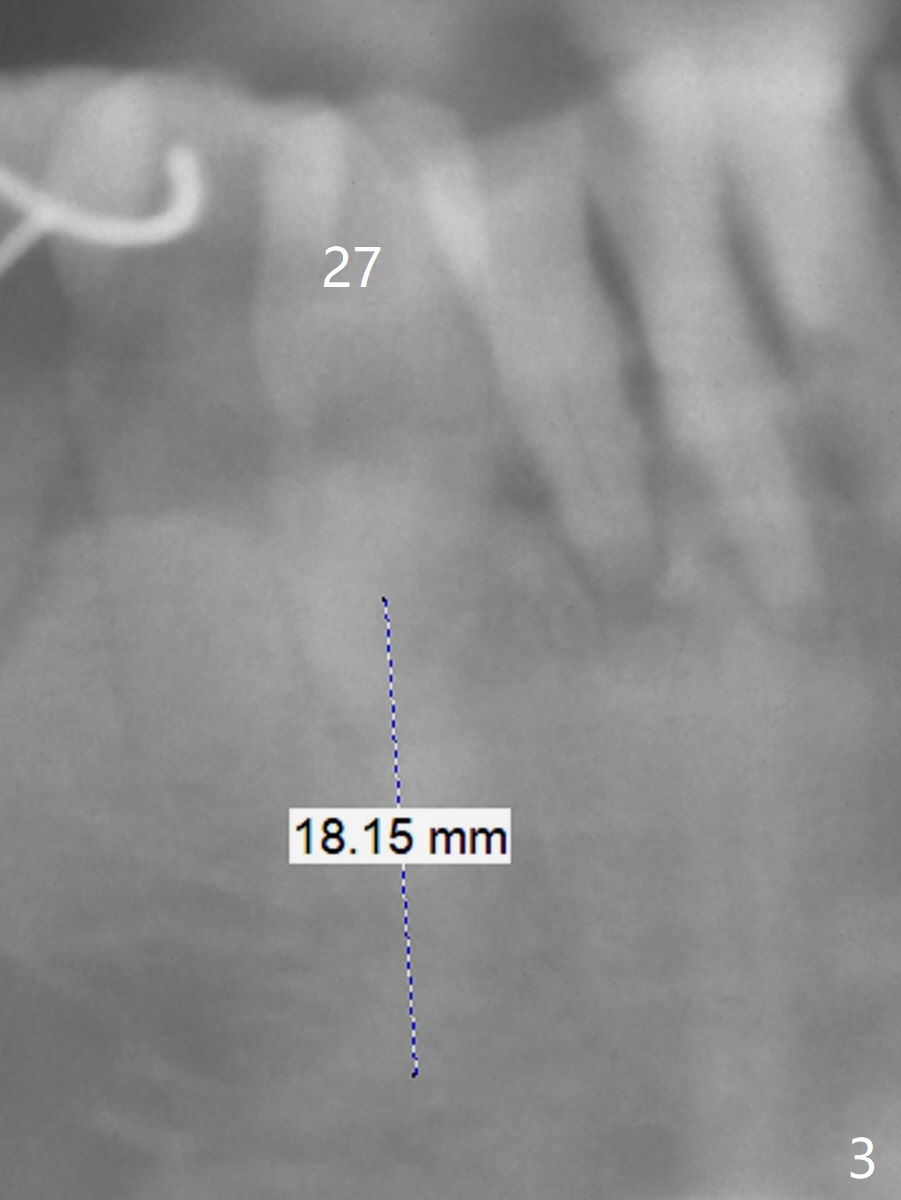

A 73-year-old man has poor dentition with lack of posterior support (Fig.1). The teeth #24-26 were mobile > 1 year ago (Fig.2), while the tooth #27 is reportedly now. To counter heavy mastication, long implants are to be placed (Fig.3). Take preop photos and PAs.